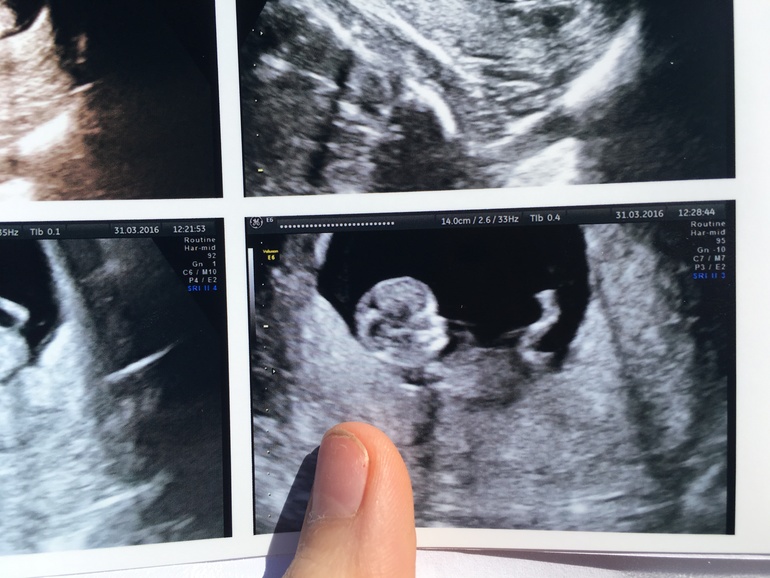

1 скриннинг + фото

Вопросы про УЗИ, обследования и анализы: что, где, как, когда?Была на первом скринниниге, по крови все отлично , Узи тоже отлично . Я не ожидала увидеть маленького человека! Была с мужем, реакция что его, что моя были одинаковые - ступор 😃! Малый ( надеюсь , мальчик будет) спал все Узи ! узистка была довольна сном ребёнка, потому что спокойно все измеряла . Я ожидала увидеть хоть какие-то движения.. Но он спал с рукой во рту .. Все размеры , как по книжке , кровь тоже вся в норме, никаких там отклонений. Показывали и нос, и рот! Офигеть... 5 см , а уже все ,как у человека. Я смотрю , а он пузатый! Говорю врачу, а че он такой пузатый????? Она долго смеялась ... 😃😃 необычные ощущения , но все же никаких там милостей во мне не проснулись , все так же черства к беременности , все так же ноль эмоций. Видимо, буду плохая черствая мамаша.

Я настоятельно просила как-то его расшевелить, включили 3D Узи, долго водила , только тогда он покопошился и снова уснул..